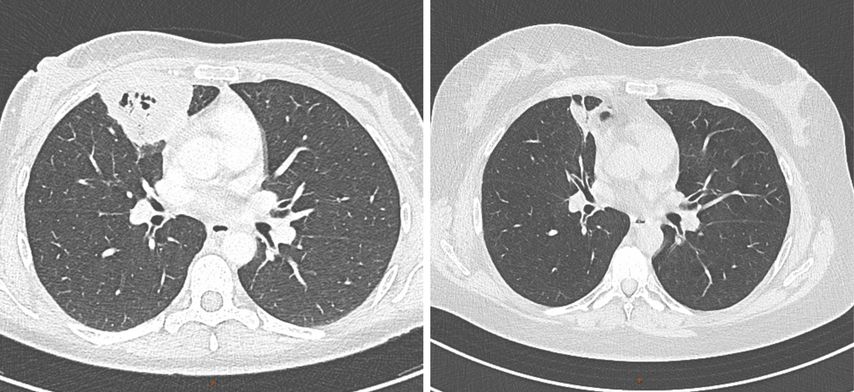

Unter der eskalierten Immunsuppression kam es zu einer bemerkenswerten klinischen und radiologischen Besserung. Die Entzündungswerte normalisierten sich rasch und sowohl die pulmonalen Infiltrate (Abb.2) als auch der Pseudotumor an der Schädelbasis begannen in der Bildgebung zu schrumpfen. Auch die neurologischen Defizite zeigten sich rückläufig, wenngleich dieser Prozess deutlich langsamer verlief.

Abb. 2: Thorax-CT vor (links) und nach Einleitung der Therapie (Quelle: Universitätsklinik für Radiologie Innsbruck)